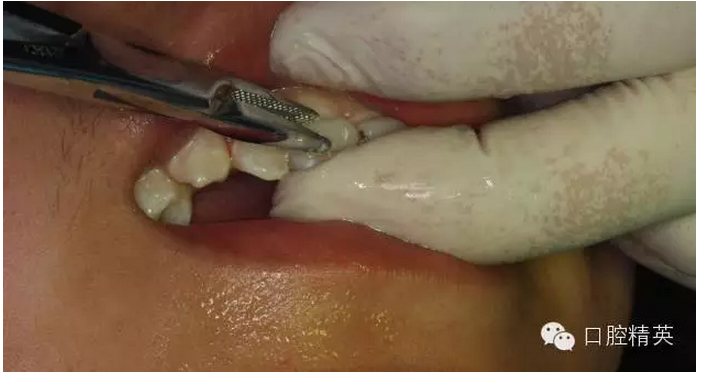

圖12.局部浸潤(rùn)麻醉

圖13.清理21牙槽窩